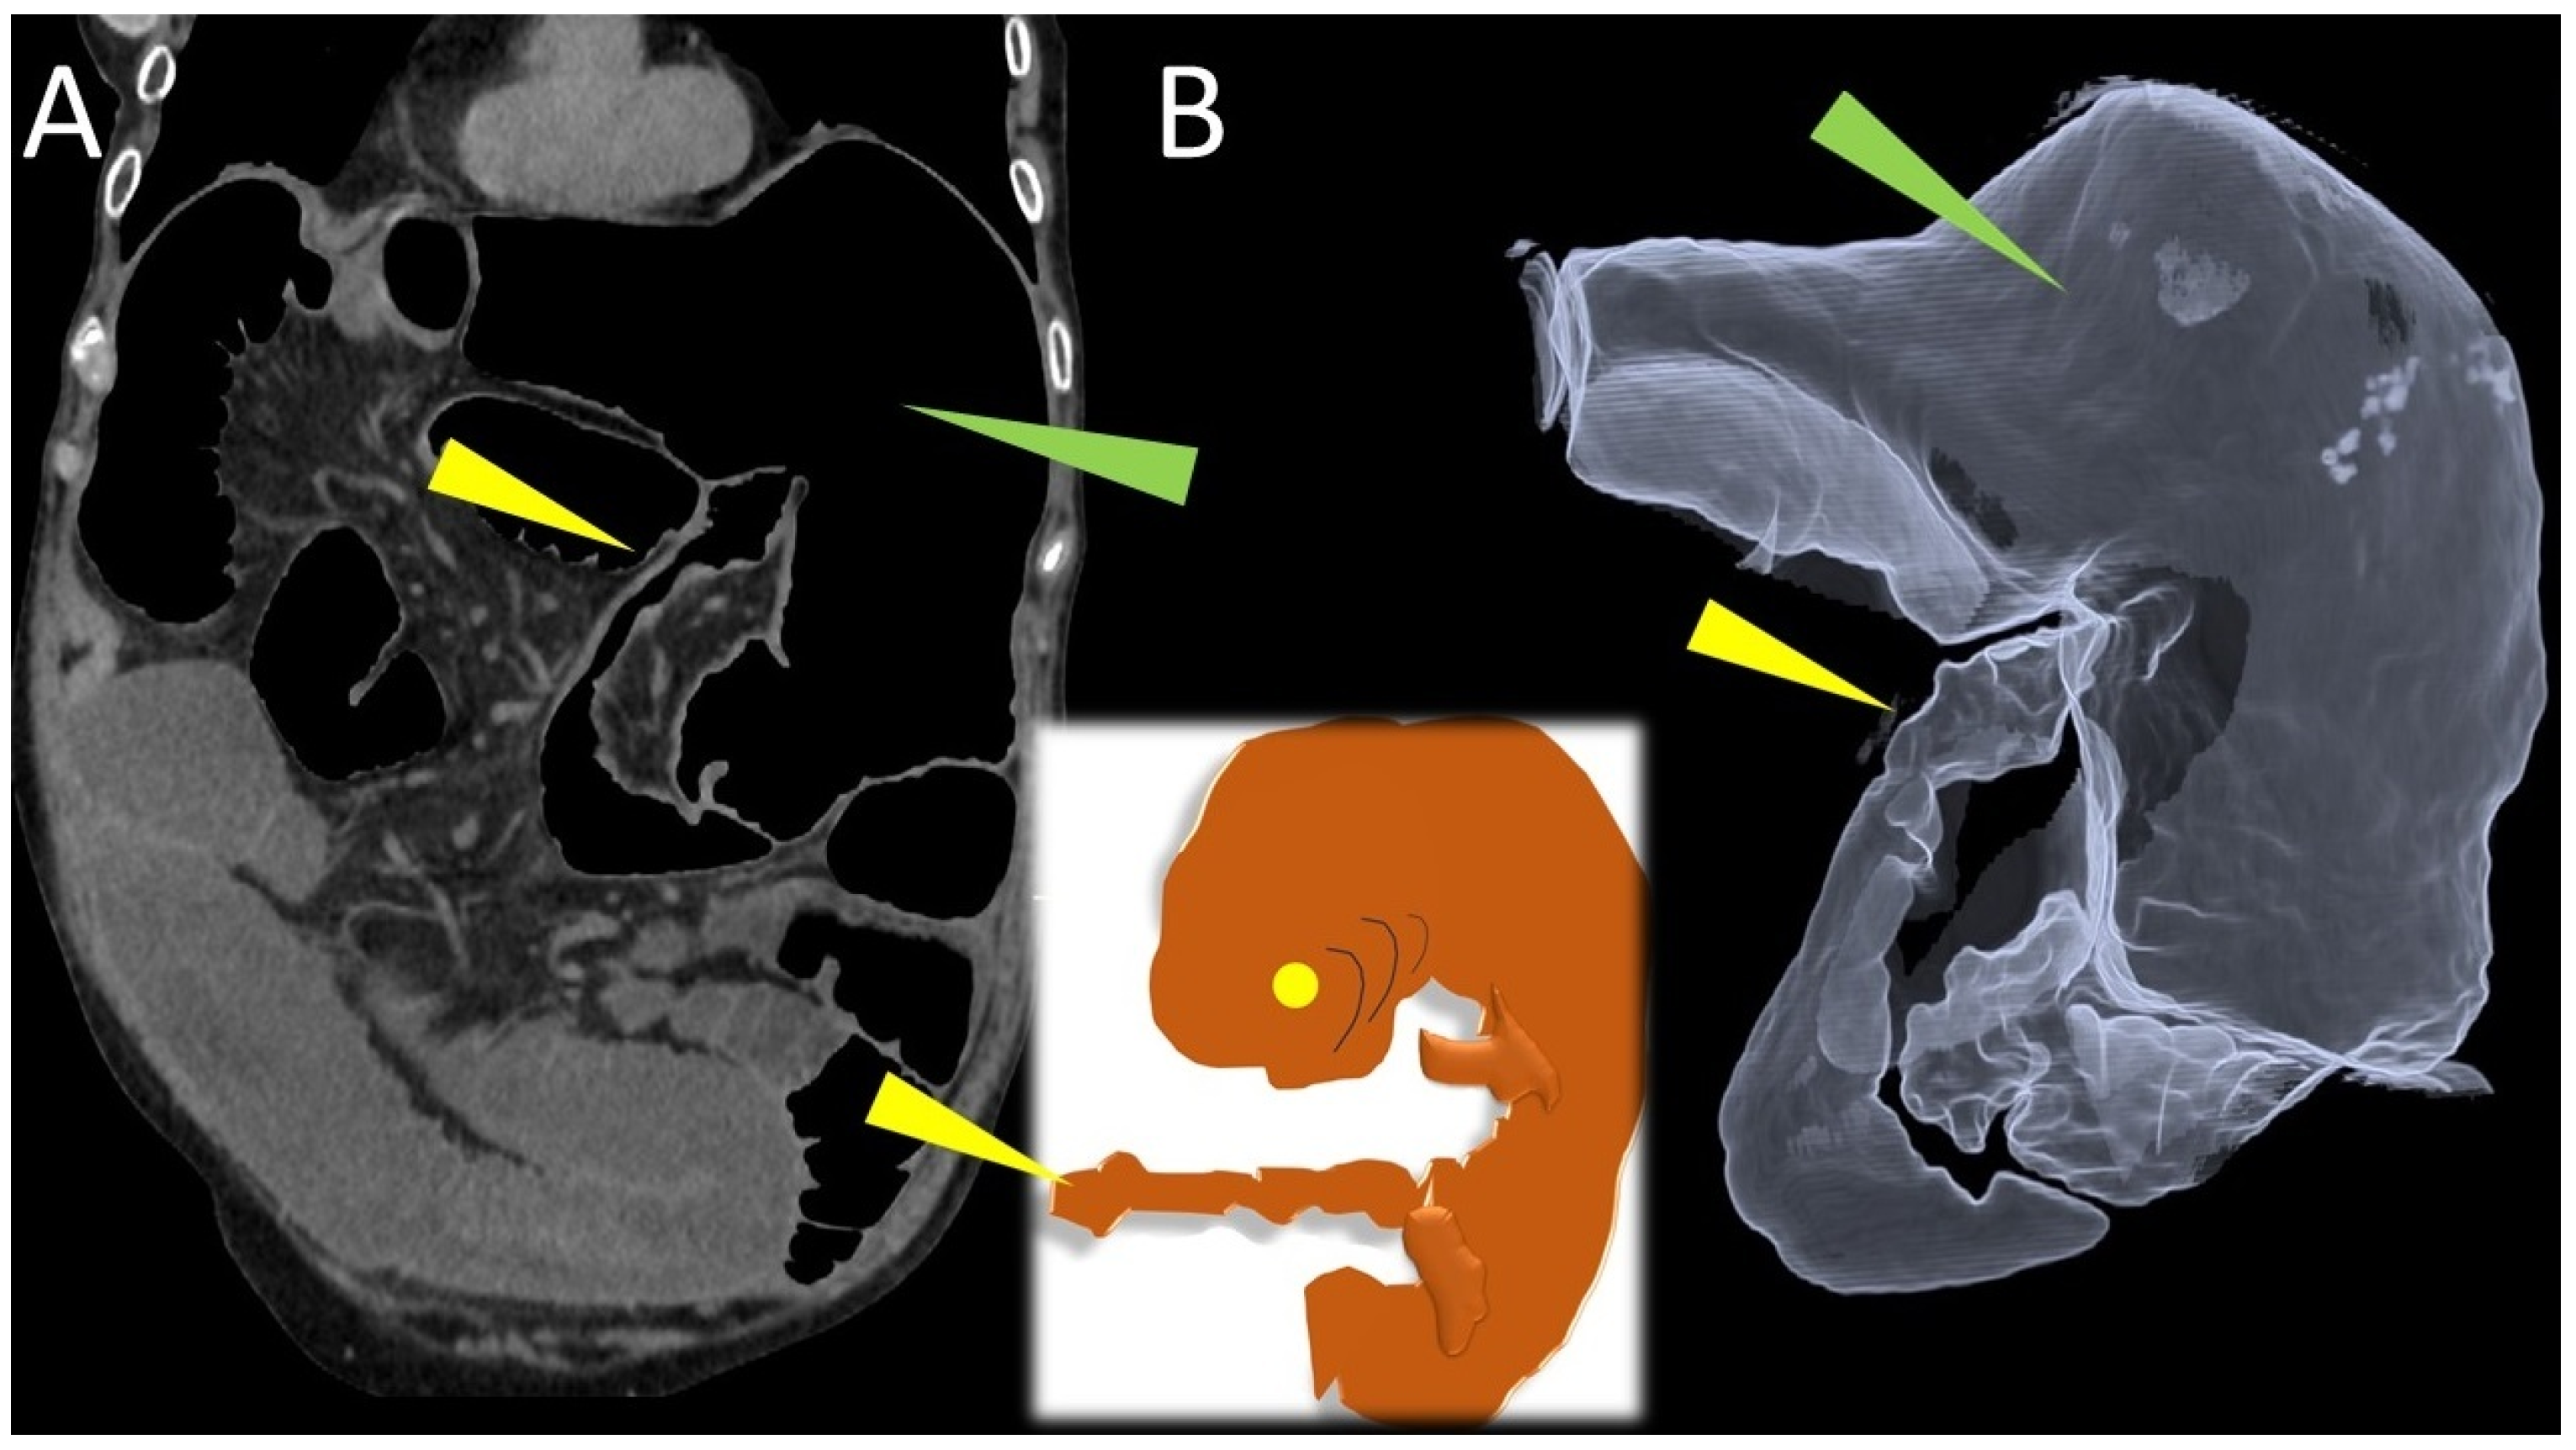

Embryo Sign on Abdominal CT as the Footprint of Cecal Volvulus: Improved Practice Through Lessons Learned from a Case Report

Pierro, A.; Posa, A.; Mirco, P.; Di Maio, D.; Vallo, A.; Lippi, M.; Cristino, R.; Barbieri, P.; Oriente, P.; Totaro, A.; et al. Embryo Sign on Abdominal CT as the Footprint of Cecal Volvulus: Improved Practice Through Lessons Learned from a Case Report. Life 2025, 15, 1873. https://doi.org/10.3390/life15121873